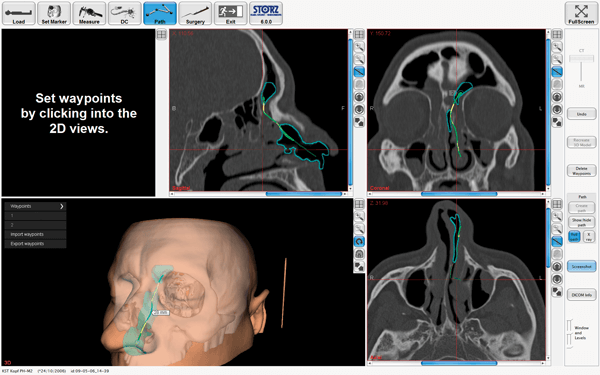

Figure 2. Preoperative planning of pathways to e.g. the frontal sinus on navigation devices.

Computer-assisted navigation offers augmented reality tools to mark pathways for easier access to critical structures according to CT anatomy or mark them giving optical and/or acoustic feedback to the surgeon (see Figures 2 and 3). This can be especially helpful in an unclear surgical field. With the advent of stronger MRIs (>5 Tesla) tractography of white brain matter for example becomes more sensitive, and thus critical neurological deficits postoperatively can be avoided with better preoperative planning and intraoperative navigation [8].